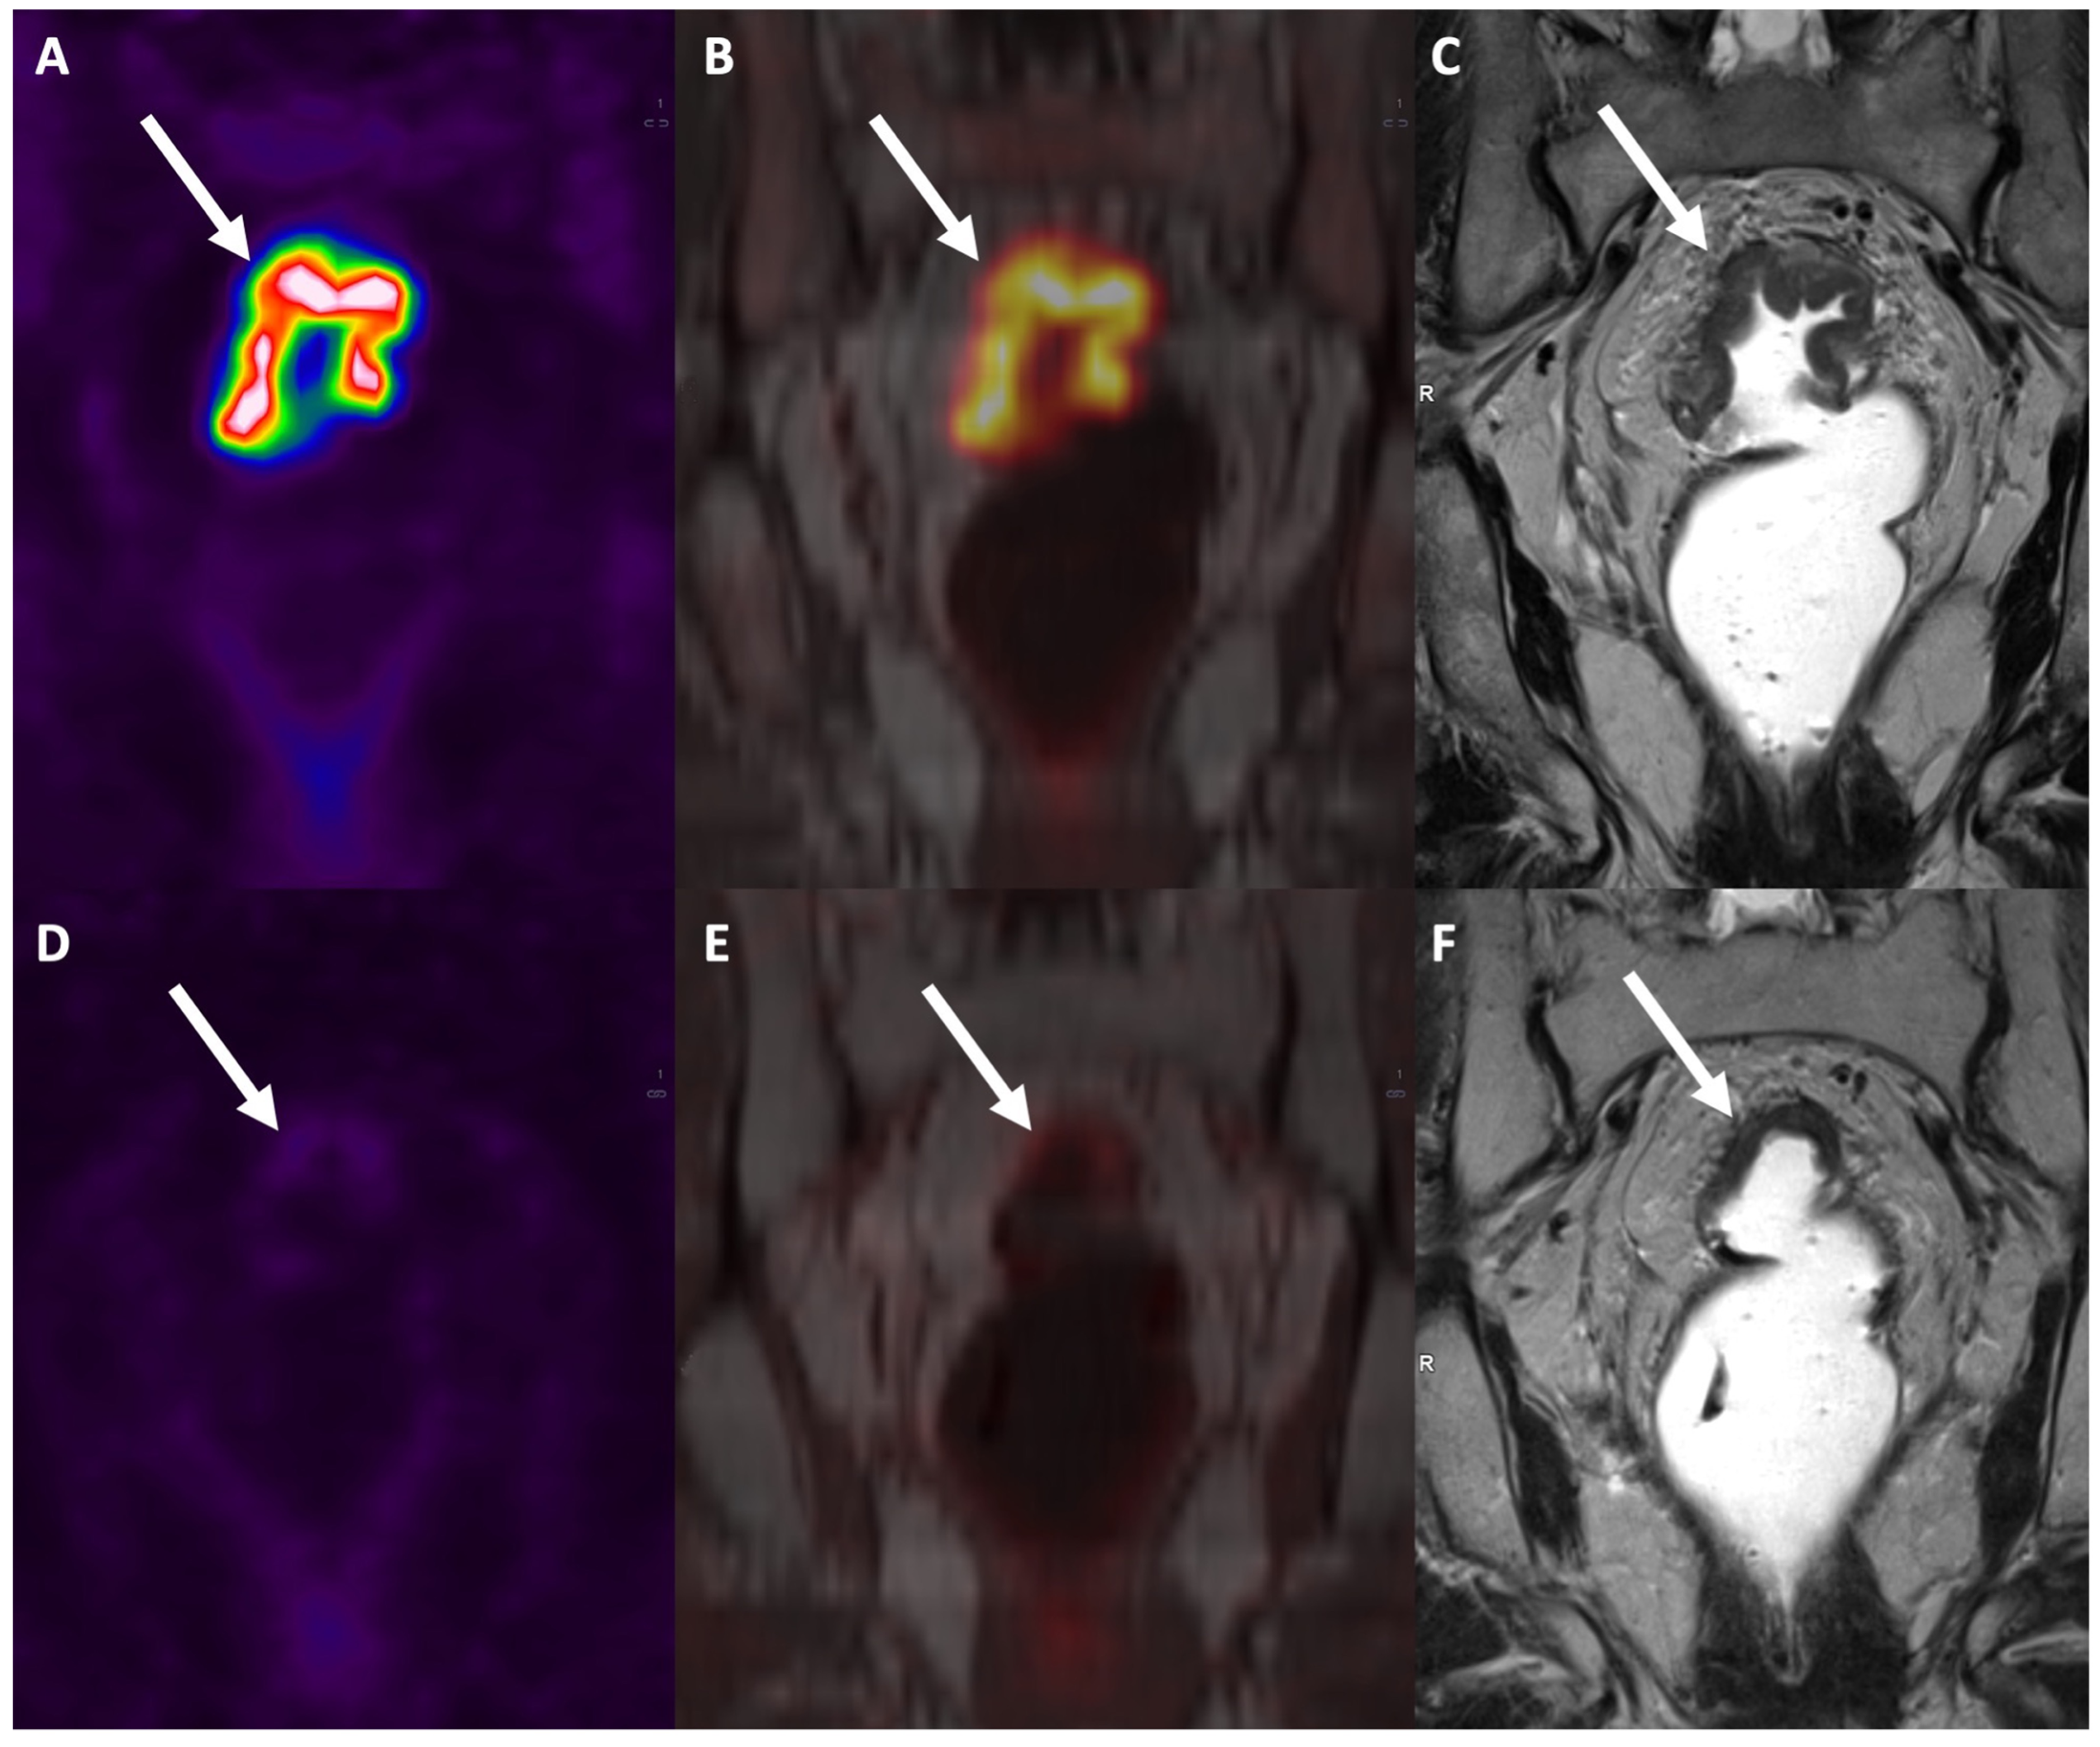

- Jayaprakasam, V.S.; Ince, S.; Suman, G.; Nepal, P.; Hope, T.A.; Paspulati, R.M.; Fraum, T.J. PET/MRI in colorectal and anal cancers: An update. Abdom. Radiol. 2023. [Google Scholar] [CrossRef]

- Mirshahvalad, S.A.; Hinzpeter, R.; Kohan, A.; Anconina, R.; Kulanthaivelu, R.; Ortega, C.; Metser, U.; Veit-Haibach, P. Diagnostic performance of [18F]-FDG PET/MR in evaluating colorectal cancer: A systematic review and meta-analysis. Eur. J. Nucl. Med. Mol. Imaging 2022, 49, 4205–4217. [Google Scholar] [CrossRef] [PubMed]

- Crimì, F.; Valeggia, S.; Baffoni, L.; Stramare, R.; Lacognata, C.; Spolverato, G.; Albertoni, L.; Spimpolo, A.; Evangelista, L.; Zucchetta, P.; et al. [18F]FDG PET/MRI in rectal cancer. Ann. Nucl. Med. 2021, 35, 281–290. [Google Scholar] [CrossRef] [PubMed]